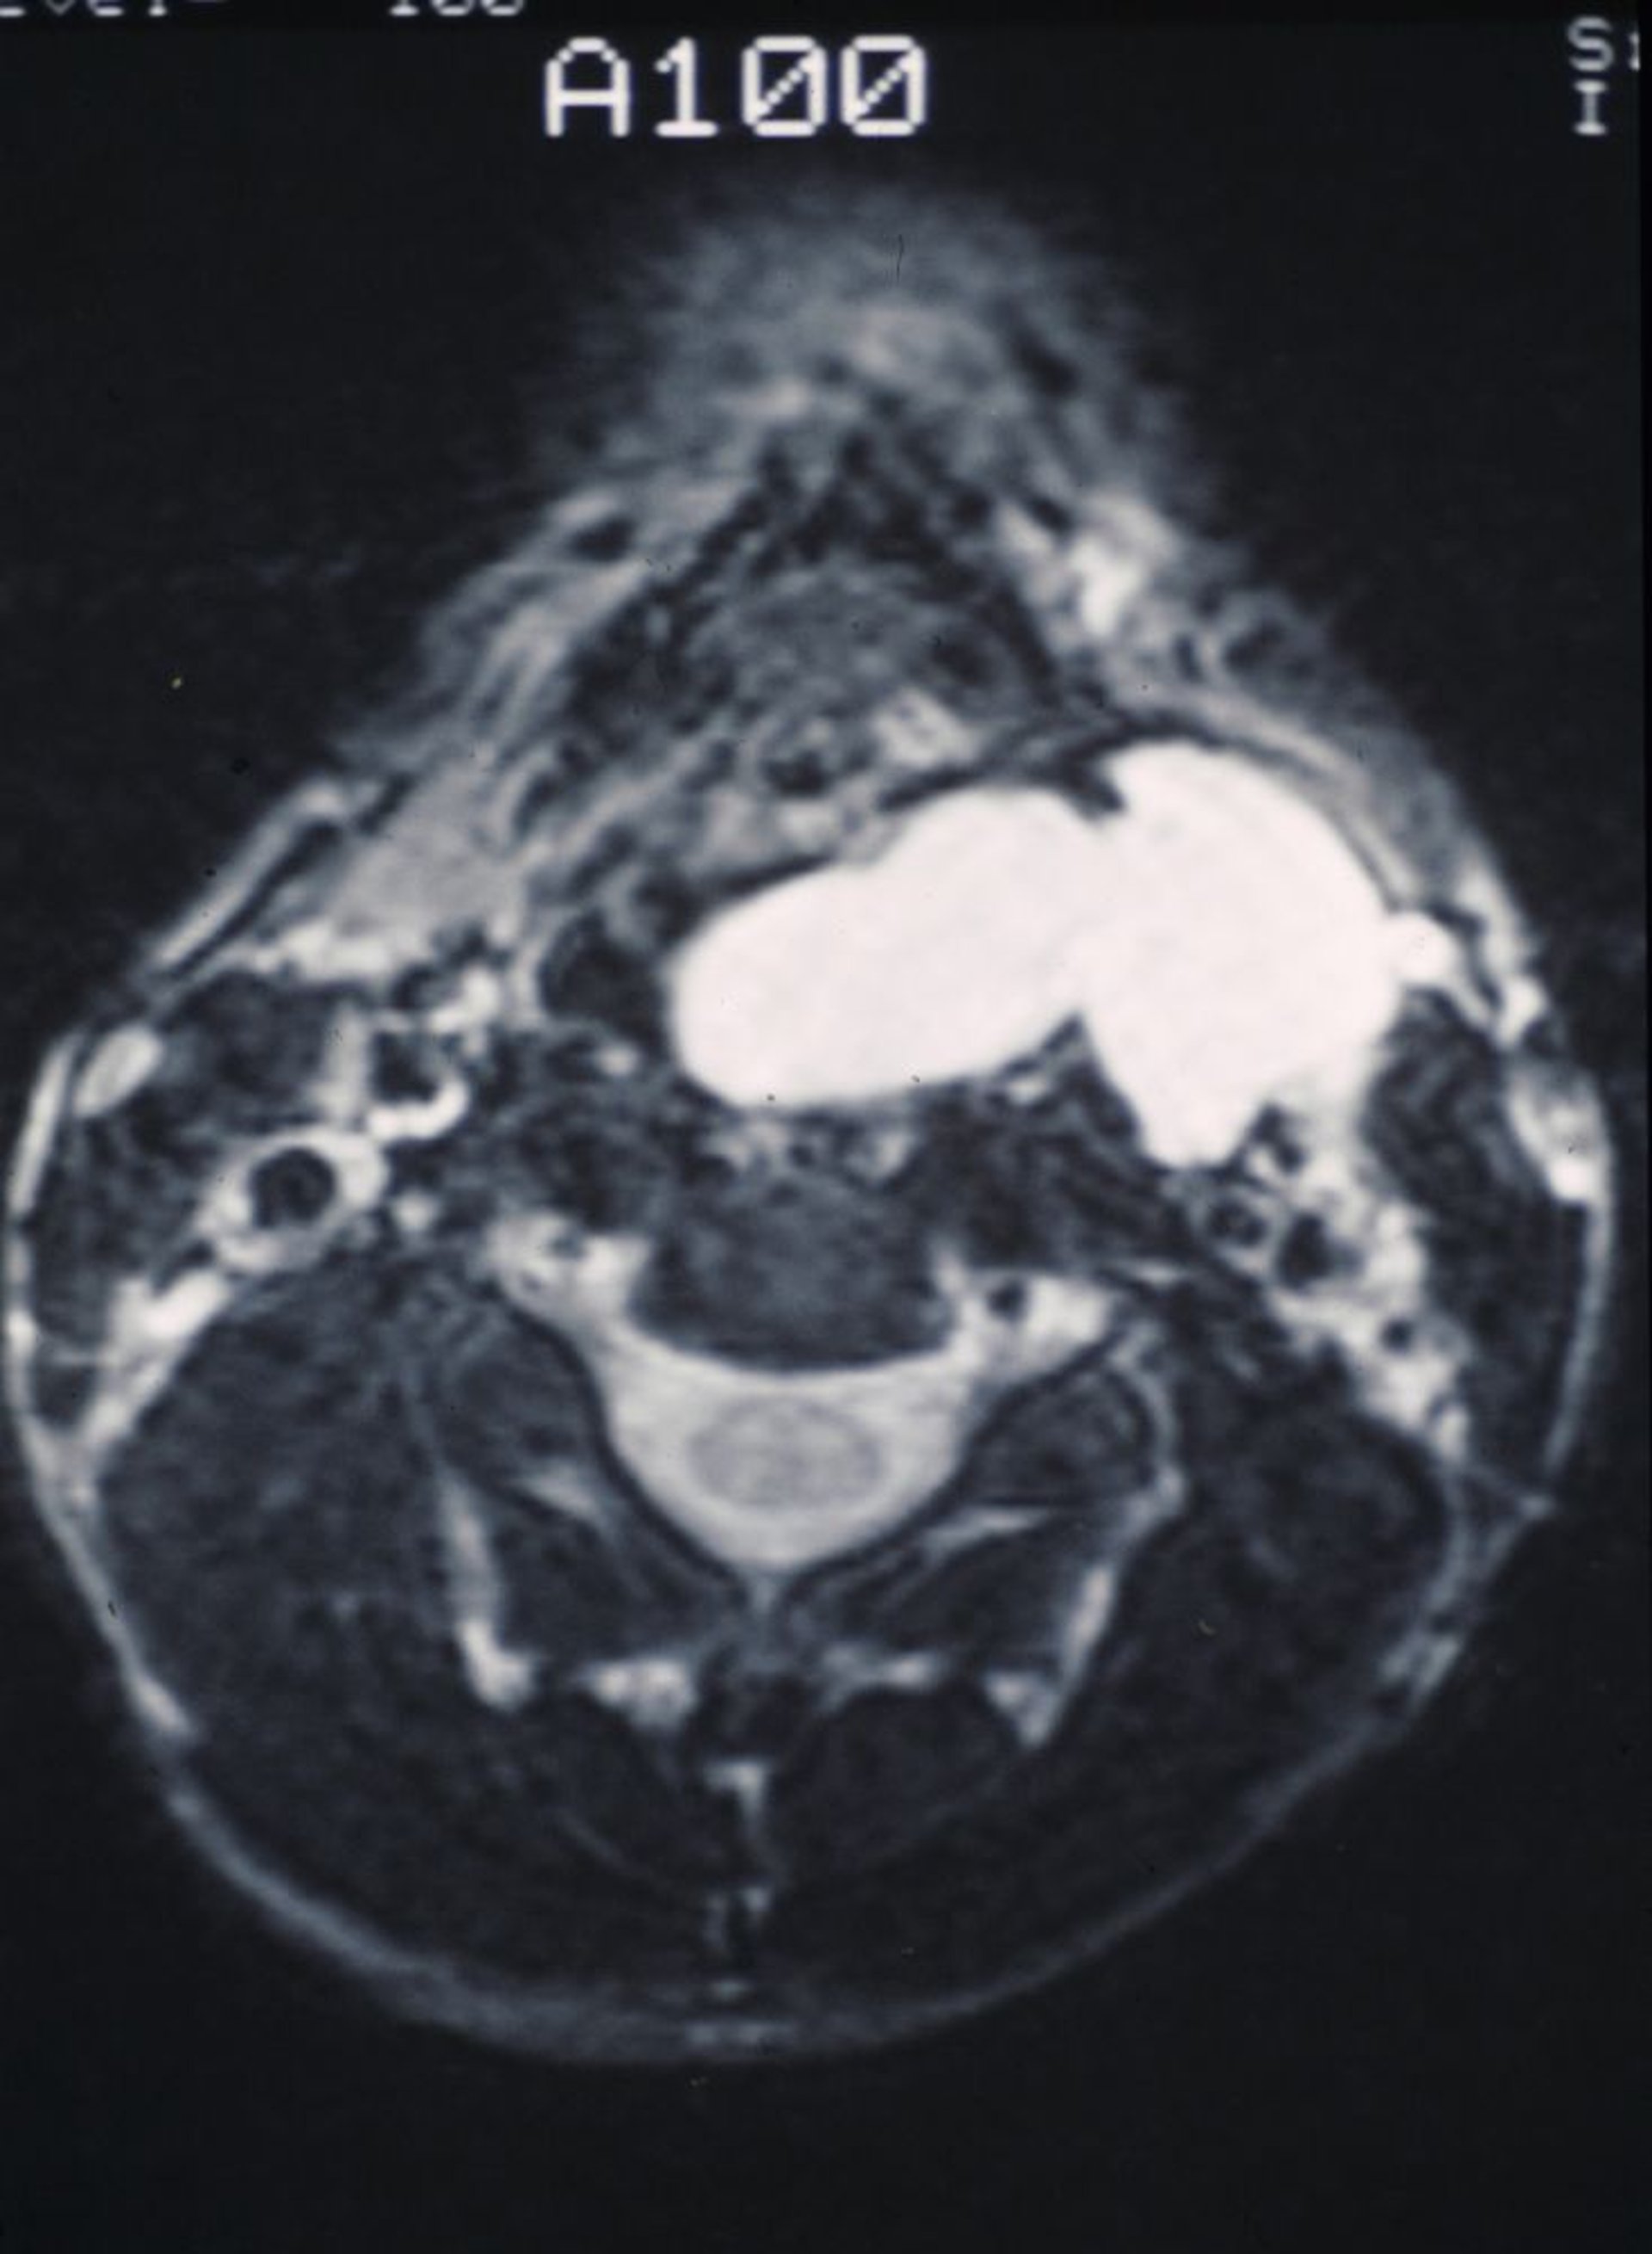

Laringocele

Esta RM muestra un laringocele liso lleno de moco que sobresale en la garganta y se exterioriza en el cuello.

Image provided by Clarence T. Sasaki, MD.